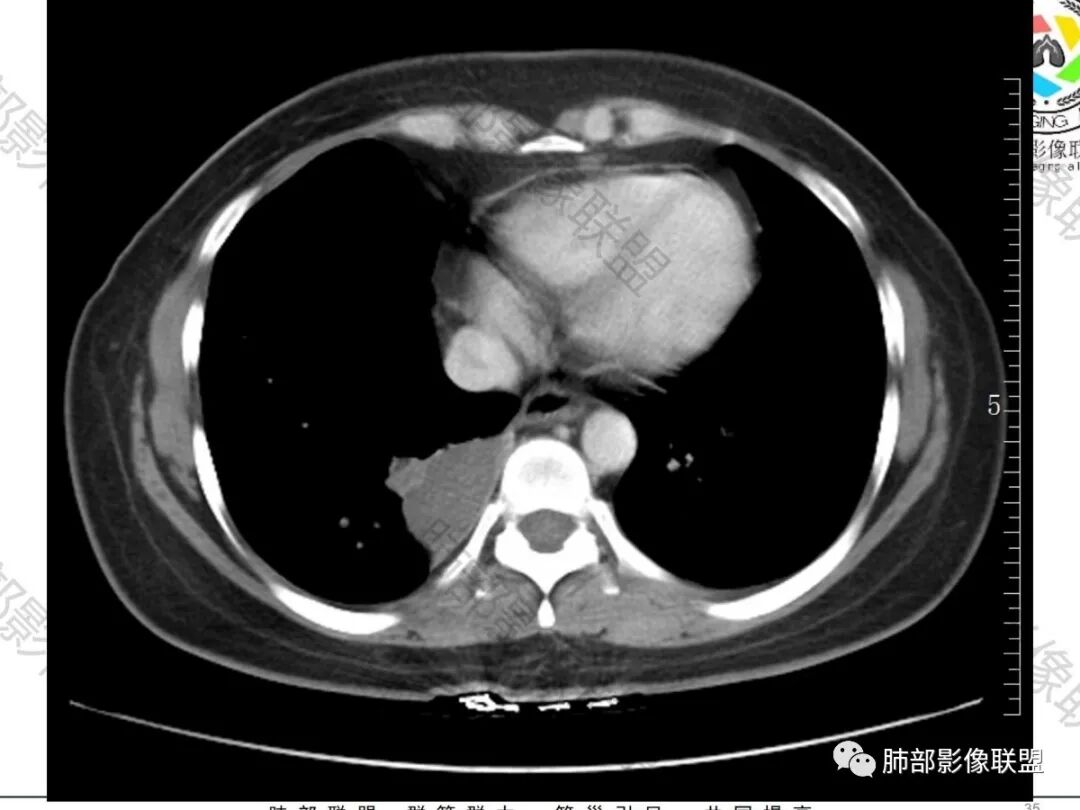

吴婧wj:    边缘平直,脂肪层清晰。与支气管关系并不密切。首先定位肺内应该没有问题。病变特点是囊性为主的,周围有一点是伴感染还是压缩肺?从这个密度来推测,可能的有:支气管囊肿,隔离肺血供不支持,结核,粘液腺癌,粘液腺瘤,肉瘤样癌。肉瘤样癌边缘不够膨隆。然后最后一个是转移。腹痛,到底有何联系,需要进一步腹部检查。

①部位及形态。多位于中下肺及内带,无感染时边缘清楚,呈圆形或卵圆形。②X线平片呈软组织密度,合并感染时内见气-液平面及邻近肺实变或边缘模糊的密度增高影。③CT检查可清楚显示其内部成分。无感染时,囊肿壁菲薄。囊内充满液体时为水样密度(0〜20HU),约50%病例因囊肿内蛋白成分、钙质及黏液而呈较高密度。10%见囊壁钙化。液体完全排出时为含气囊肿。本病常合并感染(75%),此时嚢肿迅速增大,囊壁增厚及强化,外壁变模糊,囊内出现气-液平面,形似肺脓肿,但治疗后病变可有明显变化。囊肿邻近肺组织由于压迫的活瓣样作用及侧支通气造成过度膨胀及空气潴留。④MRI T2WI 上均为高信号,T1WI 则因成分不同而为低信号、等信号或高信号,合并感染则为中等信号。

1.肺部囊样结节影,壁较均匀一致,未见强化(壁轻度强化),常见者为支气管囊肿。内容物可为气体、低密度液体、高密度液体(如伴出血或感染等)。

2.囊样结节影如外形欠规则,观察到血管样结构穿行,囊壁不均匀增厚或呈现壁结节,结节外边界较清楚磨玻璃晕等,应想到恶性病变可能。

3.如灶周未见明显渗出,患者缺乏呼吸系统临床症状,不宜轻易冠以“感染”的诊断意见。

4.支气管囊肿伴曲霉菌寄生临床常见。

本例未出现曲霉菌感染或寄生的影像学特征,未做出相关判断在情理之中。

病理曲霉诊断出乎预料。